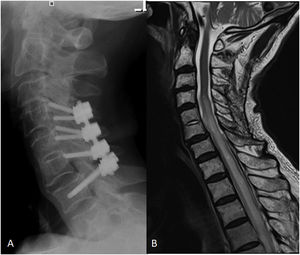

Further image studies were performed. Cervical X-ray showed hypodense areas of C5/C6 vertebral bodies and prevertebral calcification compatible with an abscess (Fig. 1A). Computed tomography (CT) demonstrated a prevertebral collection and a radiolucency of anterior cortical margin of C5-C6 (Fig. 1B). Magnetic resonance imaging (MRI) reported a prevertebral collection with sinus tract from the esophagus, C5/C6 osteomyelitis and an epidural abscess with subarachnoid space occupancy and associated increased uptake of cervicodorsal perimedular ependyma (Fig. 1C). The patient developed a spondylodiscitis and epidural abscess after a previous, four weeks before, neglected esophageal perforation.

A. Cervical lateral radiograph: hypodense lesions of C5/C6 vertebral bodies with slight listhesis from C4 to C5. Prevertebral calcification is compatible with abscess formation and increased anterior soft tissue volume (arrows); B. Cervical lateral computed tomography shows erosion and radiolucency of the anterior aspect of C5/C6 vertebral bodies (arrow); C and D. Cervical sagittal T2 and STIR weighted contrast magnetic resonance showing prevertebral collection, increased prevertebral space (double arrow) associated with osteomyelitic signs in the C5/C6 vertebrae, sinus tract from the esophagus and epidural abscess with mild obliteration signs of the spinal cord (arrow).